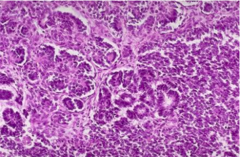

Comedo type

-subtype of DCIS -shows necrosis -high grade 3 -solid or comedo growth patterns -high grade ductal carcinoma in situ, if there is a corresponding variation in nuclei or evidence of necrosis.